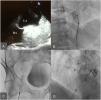

We planned the percutaneous closure of the PFO with transitory balloon occlusion to ensure accurate right ventricular tolerance of the PFO closure. Due to the clinical characteristics of the patient, with difficult intubation secondary to the parotid tumor, transthoracic echocardiogram (TTE) was used to motorize the procedure. After canalizing the right femoral vein and the right radial artery, pulmonary artery pressure was measured, ruling out significant pulmonary hypertension. Balloon occlusion of the PFO was then performed, maintaining an inflated 18 mm balloon for 10 minutes through the foramen. A significant improvement in peripheral oxygen saturation was observed, with good hemodynamic tolerance (Figure 1).

Initial closure of the defect using a cribriform patent foramen ovale (PFO) device. A: Transesophageal echocardiogram image where a PFO can be observed, with right-to-left shunt (arrow) and hypertrabeculation of the right atrium (RA) (ventricularization of the RA) (asterisk). B: Transitory occlusion test. C&D: Cribiform PFO closure device released at the PFO, radioscopy image (C) and three-dimensional transesophageal echocardiogram (D).

We then decided to perform the percutaneous closure of the PFO using a cribriform occluder. A 9 French sheath was placed in the left atrium and a 25 mm Amplatzer Multi-Fenestrated Septal Occluder - “Cribriform” (AGA Medical Corporation, Golden Valley, MN, USA) was advanced through the PFO, with good apposition of the discs before delivery.